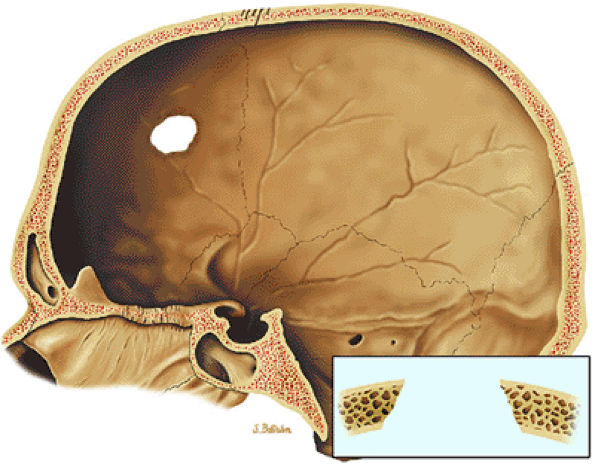

|

FIGURE 14-59 ● Langerhans cell histiocytosis of the skull. Osteolytic lesion in the frontal bone with sharp margins, giving it a punched-out appearance. Uneven involvement of the inner and outer tables results in beveled appearance.